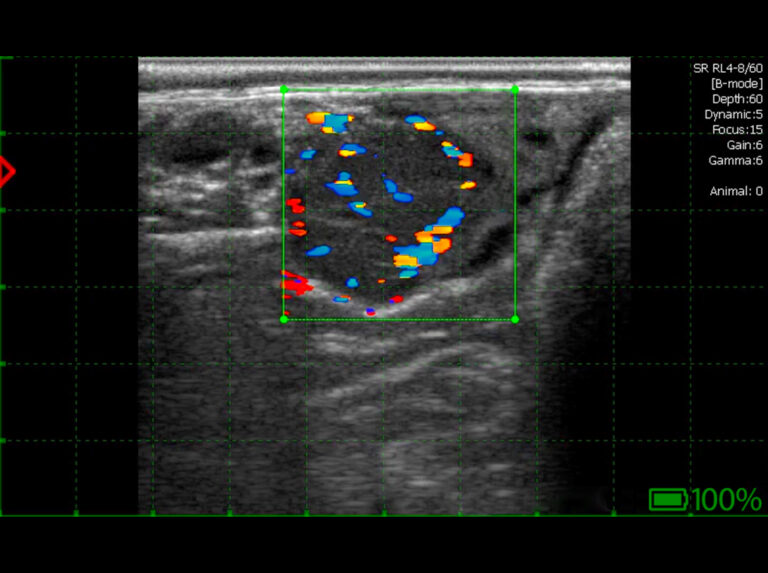

Dramiński S.A. Tecnología moderna con respeto por la tradición Blog Todos Agricultura Animal Breeding Cría Medicina Veterinaria Animal Breeding Veterinaria Doppler en la reproducción del ganado vacuno lechero Leer más Animal Breeding Veterinaria Vale la pena el Doppler en la reproducción del ganado vacuno lechero? Leer más Agricultura Floración de la colza de invierno en 2025: protección y cuidado de los polinizadores Leer más Veterinaria Haga coincidir la aplicación con su dispositivo de ultrasonido portátil! Leer más Veterinaria Pruebe el ecógrafo en la práctica! ¡Solicite una demostración antes de comprar! Leer más Animal Breeding Veterinaria Quistes ováricos, quistes foliculares y quistes lúteos Leer más Animal Breeding Veterinaria Aciclicidad y disfunción ovárica Leer más Animal Breeding Veterinaria El ciclo reproductivo normal de la vaca y la anatomía ovárica Leer más Animal Breeding Veterinaria Control hormonal de la reproducción bovina Leer más Paginación de entradas 1 2 3 4 5